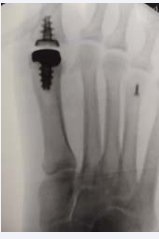

The Arthrosurface implant consists of a metatarsal component and a phalangeal component designed for resurfacing the 1st metatarsal head and the base of the proximal phalanx. These two implants replace the metatarsophalangeal joint by complete functional preservation of the joint and maintaining of the sesamoid complex (Figure 8).

Figure 12: Insertion of both implant components.

Figure 13: Final placement of the Hemi CAP DF Articular Component and DF Articular Component prior to closure.